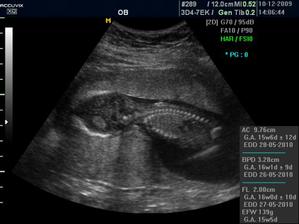

16+1 geneticka konzultace OK,nemusíme na AMC

Zaplatila jsem si ale přesto UTZ a vypada to,že budeme mit chlapečka 🙂) pry tak na 80% jistota je vždy až po porodu 🙂)

CHLAPEČEK POTVRZENY Dr Břeštákem ))